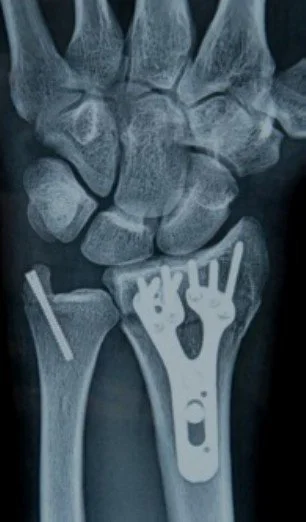

Arthritis Wrist and Forearm Childrens Wrist Fractures Colles Fractures Colles Surgery Chronic Forearm Compartment Syndrome De Quervains Syndrome Kienbocks Disease Scaphoid Fractures Scpholunate Ligament Tears TFC Tears Wrist Arthritis - Salvage Procedures Wrist Arthroscopy Wrist Exercises Wrist Xrays - Radiographers